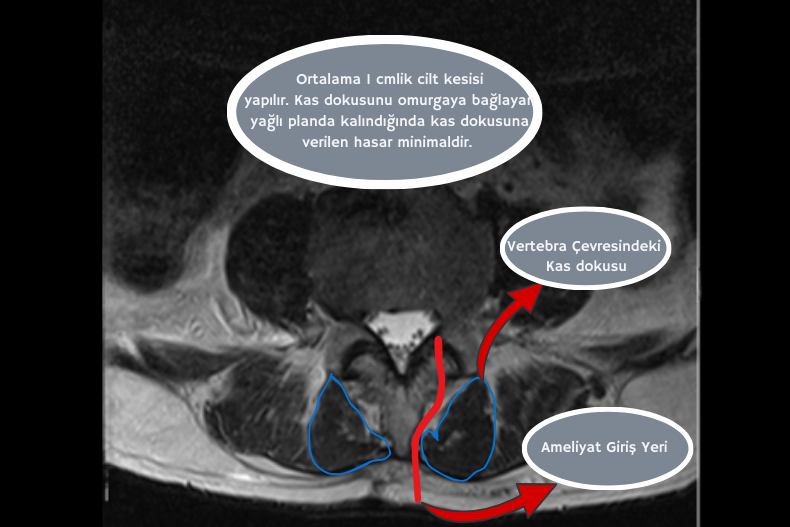

Bu ameliyatta, omurgayı çevreleyen kaslar kesilmez veya kemikten sıyrılmaz. Bunun yerine kas grupları arasındaki doğal yağlı planlar ve anatomik boşluklar, vücudun kendi yapısı kullanılarak birer koridor gibi değerlendirilir.

Mini ekartör yardımıyla kas lifleri nazikçe ayrılır ve fıtık bölgesine ulaşılır. Genellikle ortalama 1 cm’lik küçük bir cilt insizyonu yeterlidir ve ameliyat yüksek çözünürlüklü cerrahi mikroskop altında gerçekleştirilir.

Genellikle ortalama 1 cm’lik küçük bir cilt insizyonu yapılır. Mini ekartör yardımıyla kas ve kemik boşluğu kullanılarak fıtık bölgesine ulaşılır. Yüksek çözünürlüklü mikroskop altında cerrahi gerçekleştirilir.

Anatomik planlara sadık kalmak, cerrahinin vücudun doğal yapısına saygı gösterilerek, gereksiz doku hasarı oluşturmadan uygulanması anlamına gelir. Mikrodiskektomi tekniğinde bu yaklaşımın temelini, omurga çevresinde bulunan doğal anatomik boşlukların kullanılması oluşturur.

Omurgayı saran paraspinal kaslar arasında, orta hatta ve kas grupları arasında yer alan doğal kas–kemik aralıkları, yağlı planlar ve bağ dokusu boşlukları, cerrahiye güvenli geçiş alanları sağlar. Bu anatomik boşluklar, kas liflerinin bulunmadığı ya da çok seyrek olduğu doğal koridorlar niteliğindedir. Cerrah bu koridorları kullanarak ilerlediğinde kas liflerini kesmeye veya kemikten ayırmaya gerek kalmaz.